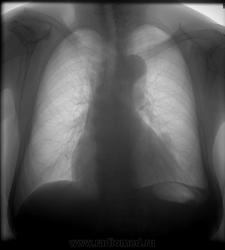

Пациентка 1932 года рождения, год назад у нее было обнаруженно периферическое образование верхней доли левого легкого. Пациентка была направленна на консультацию к онкологу. Ей было проведенно ФГДС,ФКС,ММГ,УЗИ органов бр.полости и малого таза, ничего не нашли...онколог написал заключение: СА периферического бронха? доброкачественное образование? Сегодня ровно через 10 месяцев женщина пришла ко мне на ЦФЛГ...В сравнении отмечаю незначительное увеличение образование было 1,8см х 2,0см, стало 1,8см х 2,5 см...контуры были четкими и ровными...теперь намечается вырезка по верхнему краю образования - место вхождения в образование сосуда....Хочу порекомендовать женщине КТ...КТ пока не занимаюсь, хочу спросить, отдифферинцирует ли КТ зло- от доброкачественного образования...или это необходимо сделать, для поиска источника, например в средостении? ...Почему онколог не назначил КТ легких?